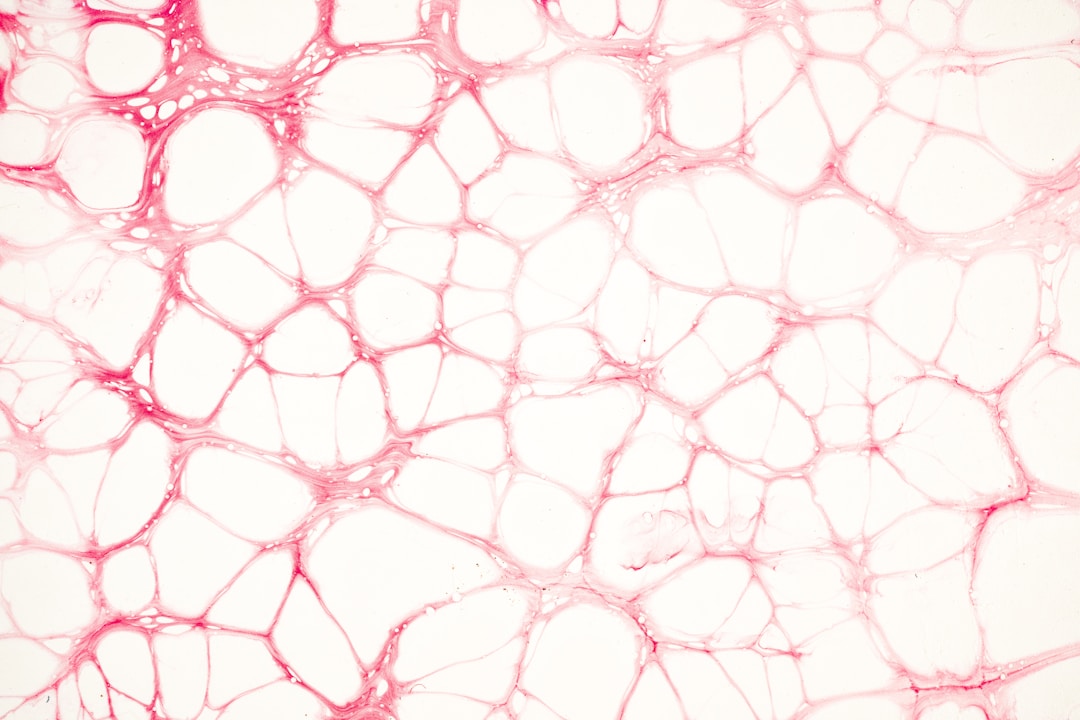

NAD+ is a vital molecule found in every cell of our body. It plays a crucial role in metabolism and is involved in various biological processes such as energy production, DNA repair, and maintaining overall cellular health. NAD+ is a coenzyme that acts as a key mediator in redox reactions, enabling the transfer of electrons from one molecule to another.